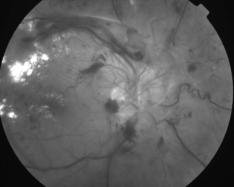

IMG0003.JPG